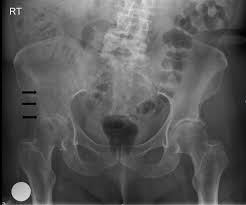

What Causes Pelvic Bone Cancer : Causes And Symptoms Of Bone Cancer - Types of biopsy procedures used to diagnose bone cancer include:. The cause of bone cancer isn't exactly known, but there are certain factors that may contribute to or increase a person's chances of forming abnormal growths in the bone. The abdomen may feel very full or heavy, and the person may also have lower back pain. Some varieties of chondrosarcoma arise from the transformation of benign cartilage lesions into cancers. Metastatic tumors of the bones are usually osteolytic, which means that they dissolve the bone and cause multiple fractures. Pelvic cancer can also occur from the spread or metastasis of other cancers from different areas of the body.

The Radiology Assistant Differential Diagnosis Of Bone Tumors from radiologyassistant.nl Osteosarcoma is probably the most common disease that is related to pelvic bone cancer, with chondrosarcoma following close behind it. The cause of bone cancer isn't exactly known, but there are certain factors that may contribute to or increase a person's chances of forming abnormal growths in the bone. Chronic pelvic pain can result from more than one condition. In contrast, some other metastatic tumors, such as those from the prostate, are commonly osteoblastic, meaning that they form new bone and increase the brittleness of the bones. Recently, doctors have recognized that some pelvic pain, particularly chronic pelvic pain, can also arise from muscles and connective tissue (ligaments) in the structures of the pelvic floor. Excluding gyn causes, ibs is the most common cause of chronic pelvic pain. Learn about the causes and risk factors for bone cancer and if there are things you can do to prevent it. And a bone that breaks.

Chronic pelvic pain can result from more than one condition. Inserting a needle through your skin and into a tumor. Bladder, uterus, and descending colon. Suggest treatment for bone cancer. The abdomen may feel very full or heavy, and the person may also have lower back pain. Pelvic cancer can also occur from the spread or metastasis of other cancers from different areas of the body. Bone metastasis may be the first sign that you have cancer, or bone metastasis may occur years after cancer treatment. Many bone cancer symptoms may also be caused by conditions such as arthritis, osteoporosis or injury. Bone metastasis can cause pain and broken bones. Surgery to remove a tissue sample for testing. Metastatic tumors of the bones are usually osteolytic, which means that they dissolve the bone and cause multiple fractures. Your bone metastases may be: It is a rare type of cancer.

bone cancer in the hip can cause pain, limping, fractures of the bone, and hypercalcemia , a condition in which there is too much calcium in your blood. Treatments which may be considered include surgery, chemotherapy and radiotherapy. In his pelvis that spread to his bones, or they were calling it bone cancer. With rare exceptions, cancer that has spread to the bones can't be cured. There are several different types. Even though the second form of bone cancer is often not said to be pelvic bone cancer, it can still cause the same types of serious damage to the pelvis and the surrounding areas. Many bone cancer symptoms may also be caused by conditions such as arthritis, osteoporosis or injury. The abdomen may feel very full or heavy, and the person may also have lower back pain. The dna mutations that cause some inherited forms of bone cancers are known. While scientists need to carry out more research into the precise cause of bone cancer, the american cancer society state that there is a range of risk factors for bone cancer, including genetics. Cancer cells that have spread to the bone can damage the bone and cause symptoms. The most common symptom is constant pain near the bone. And a bone that breaks.